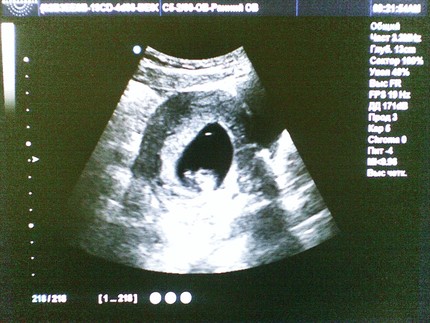

УЗИ в конце первого триместра

На первоначальное УЗИ во время беременности женщина направляется в конце первого триместра. УЗИ могут проводить либо трансабдоминально, либо трансвагинально.

На этом УЗИ выявляется количество плодов в матке, оценивается состояние эмбриона, срок беременности, а также для исключения внематочной беременности и серьезных пороков развития. Именно поэтому такое исследование очень важное.